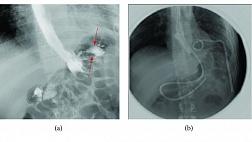

Пациенту была проведена полностенная резекция опухоли. После маркировки и подслизистой инъекции был сделан дугообразный разрез по ходу пищевода с полностенной резекцией (рис. 2 — A, B, C). Для закрытия дефекта использовалась новая петля LeCamp™ Endoloop Device (Leo Medical Co., Ltd., Китай; рис. 1 — D; 2 — D, E) и эндоскопические клипсы. Патоморфологическое исследование удаленной опухоли (рис. 2 — F) подтвердило диагноз «лейомиома». Послеоперационный период протекал без осложнений. При исследовании через 2 месяца нарушений проходимости пищевода не выявлено (рис. 2 — G).

image003.jpg

Рисунок 2 [1].